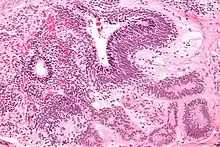

A micrograph view of dysgerminoma, showing actively dividing lobulated nuclei.[4]

Dysgerminomas are comparable to testicular seminomas and account for approximately 32- 37% of all OGCTs.[1] They are particularly prominent in individuals with dysgenic gonads of 46, XY pure gonadal dysgenesis patients.[1] Based on gross examinations, dysgerminomas are characterized by having a ‘solid, lobulated, tan, flesh-like gross appearance with a smooth surface'.[1] Microscopically, the cellular structure is distinguished by a round-ovoid shape containing ample eosinophilic cytoplasm and an irregularly shaped nuclei.[1] The uniformly positioned cells are separated through the fibrous strands and lymphocytic infiltration is commonly observed.[5]